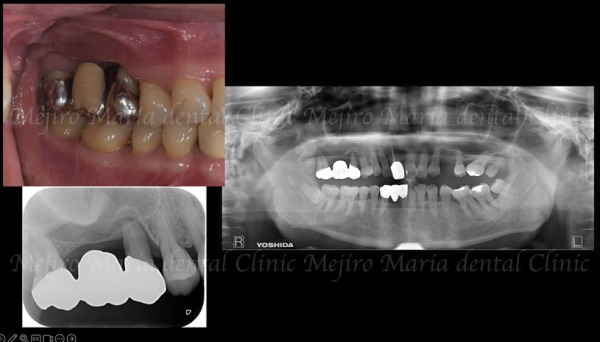

今回のように、重度の歯周病を患ってから抜歯をおこなった場合、抜歯後の歯周組織の喪失が著しくなります。特に上顎は上顎洞が近接しているため、インプラント埋入の骨量が不足することが多々見受けられます(画像赤丸○部分)。

インプラントは骨との結合(オッセオインテグレーション)によってはじめて力に耐えるため、骨が薄い、または喪失してしまった部位では、予知性が低下します。

上顎の骨量不足に対してはGBR・ソケットリフトの他に、今回のように比較的広範囲に骨が必要な症例では、サイナスリフト(上顎洞挙上術)を行うことで、インプラントを支える新たな骨を確保することができます。(外科画像1)